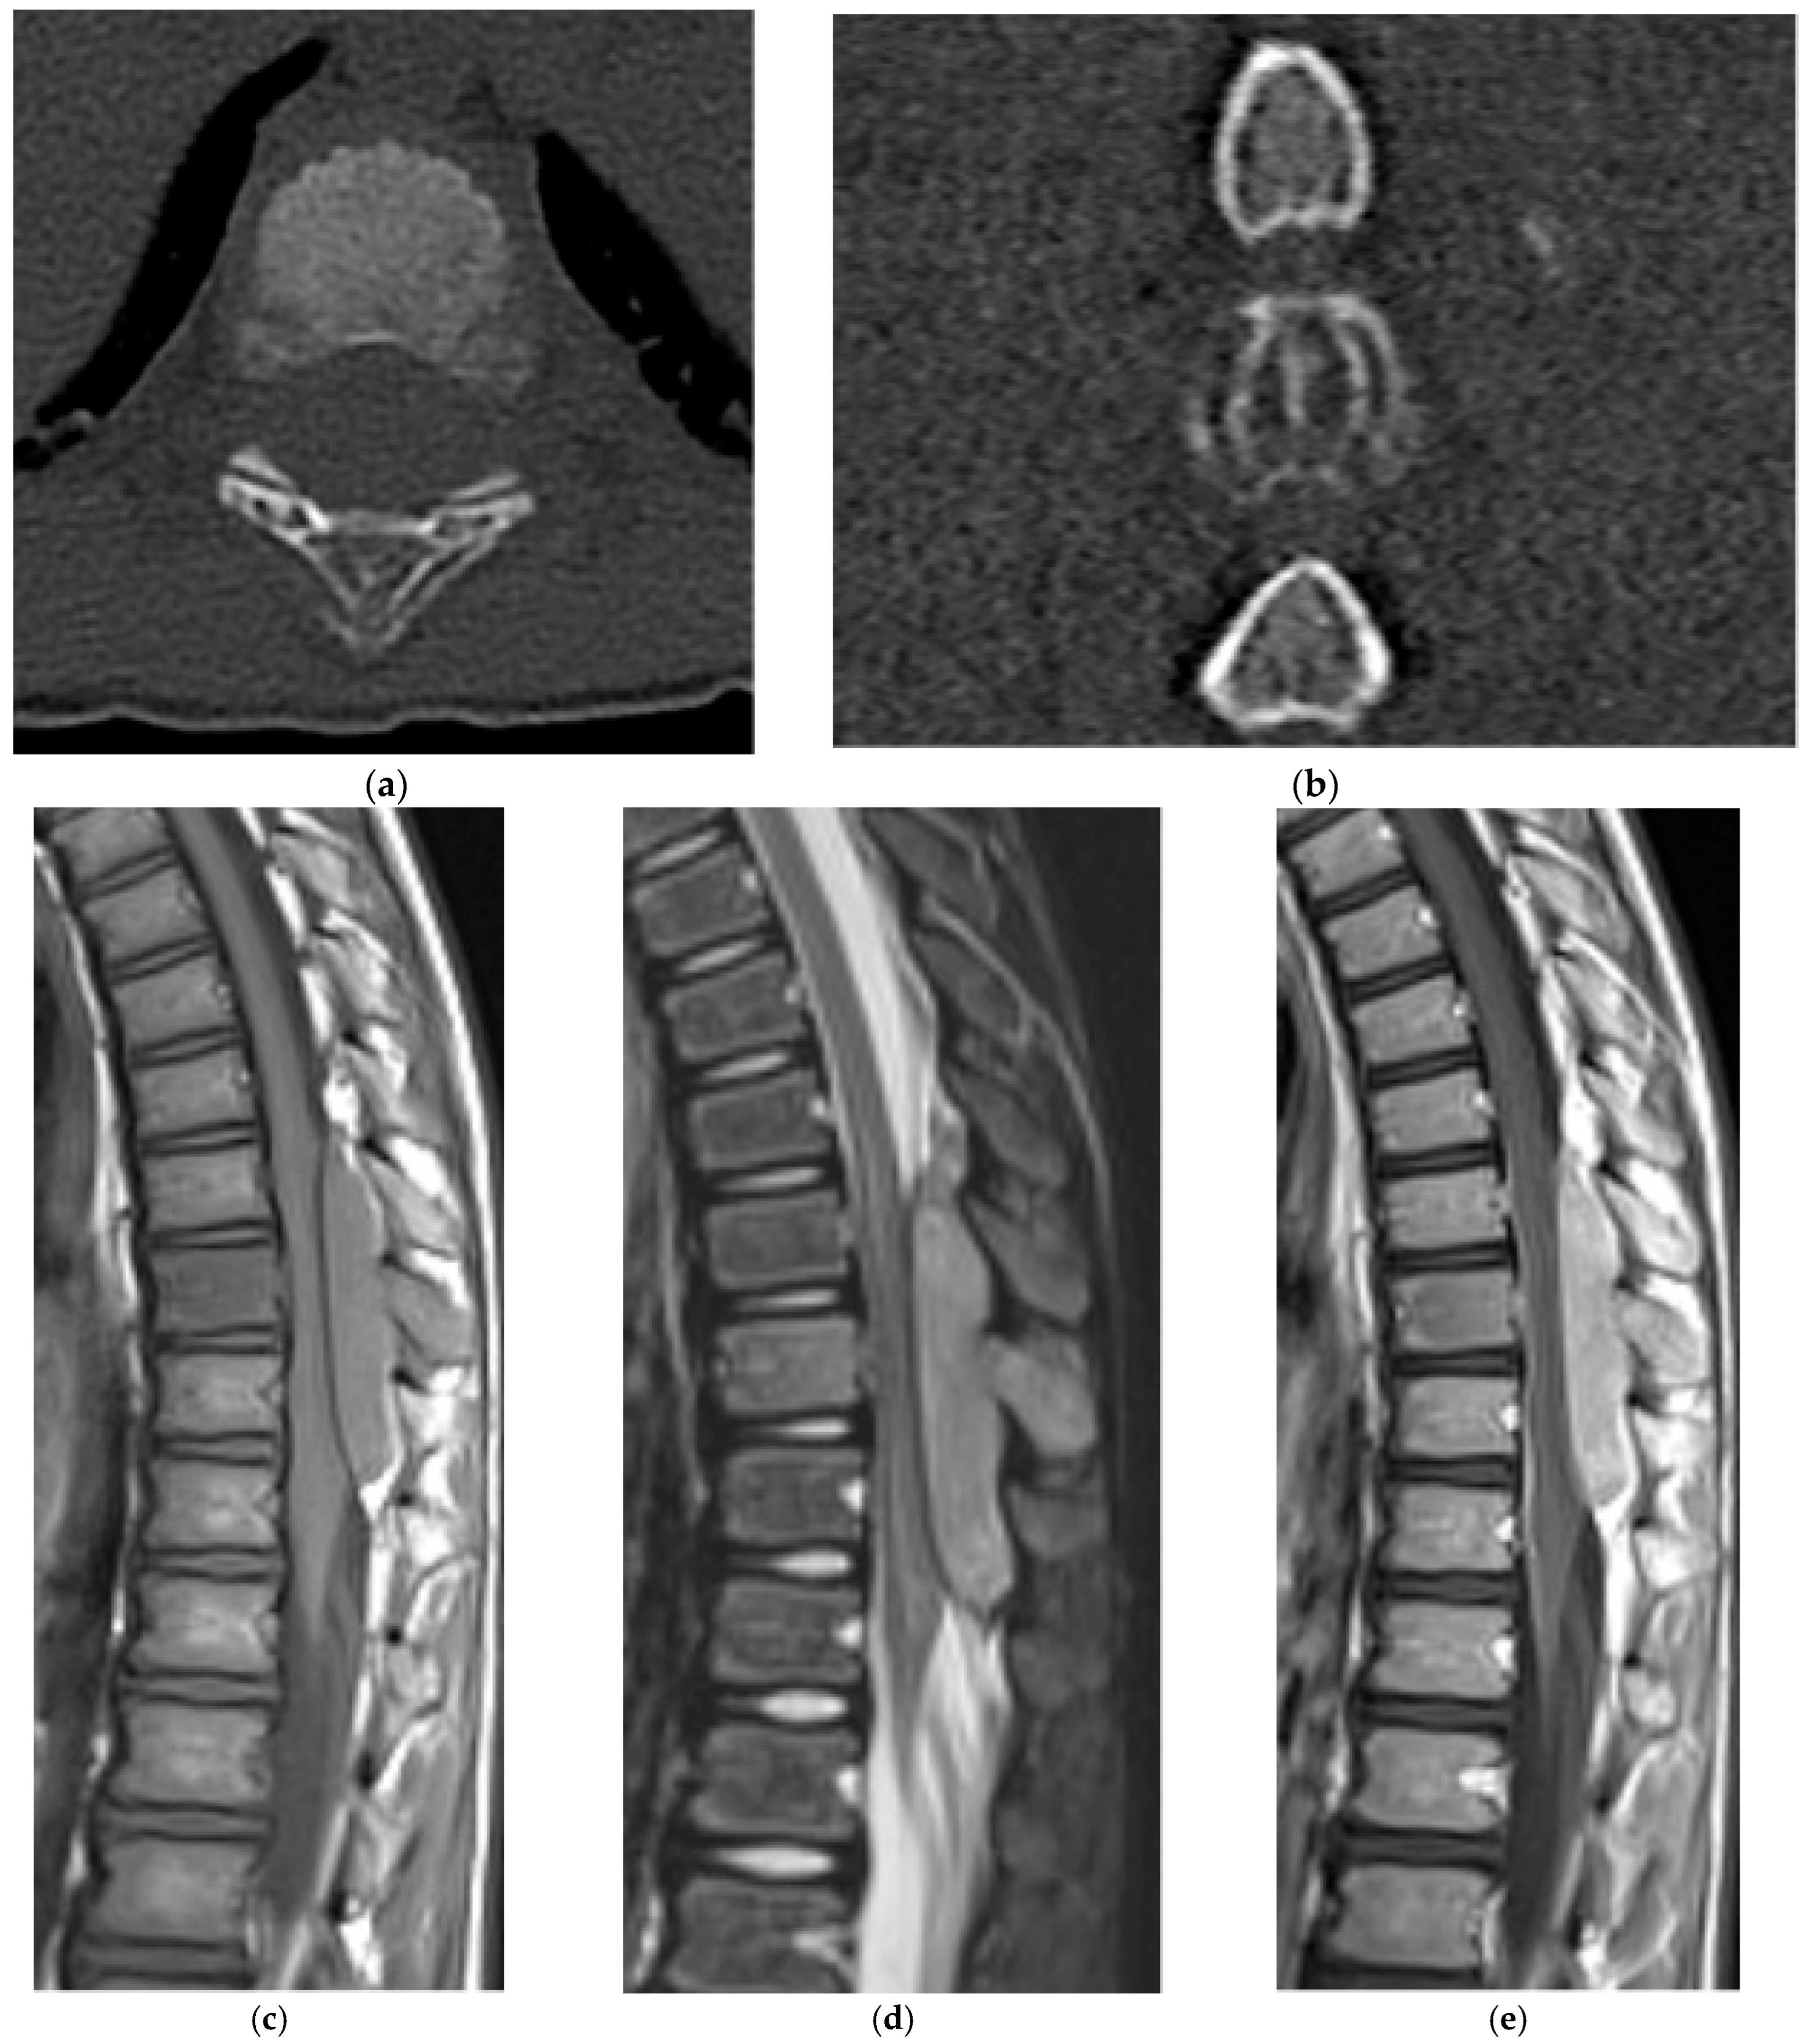

2.5.2. Aneurysmal Bone Cyst

2.6. Fibro-Osseous